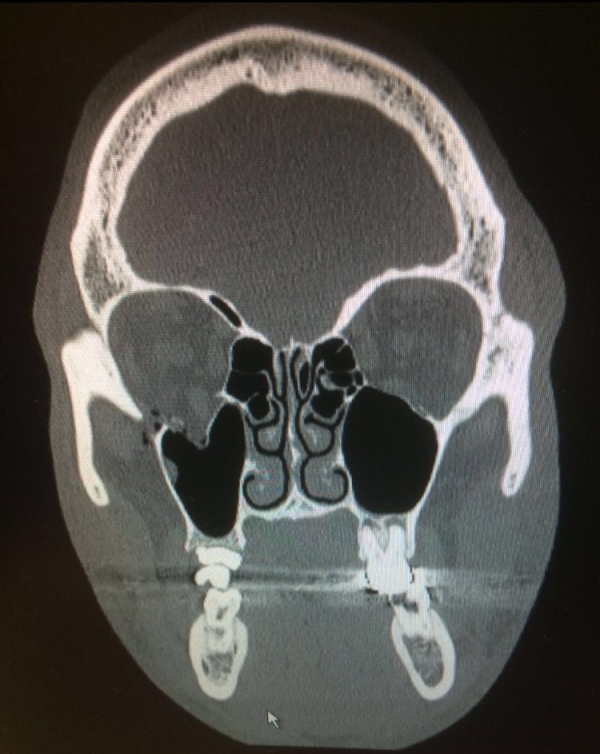

Broken eye socket. Computed tomography (CT) scan of the face (from What Is A Broken Eye Socket Breaks to any of the bones in your eye socket are referred to as orbital socket fractures. The rim of the socket is made of fairly thick bones,. A broken eye socket usually causes intense pain, swelling, and a black eye. Learn about this structure and why it’s vulnerable to injury or disease. There are several different kinds of orbital. What Is A Broken Eye Socket.